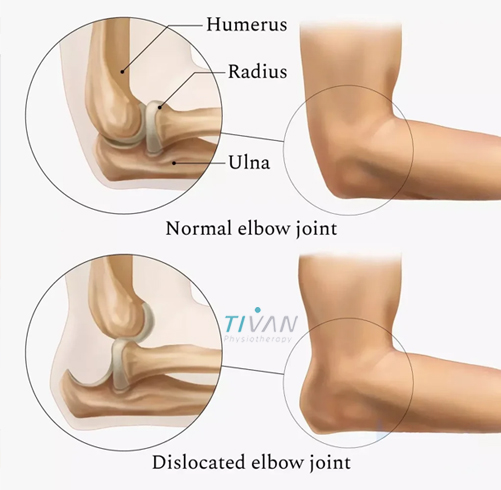

درمان در رفتگی مفصل آرنج یکی از مهمترین اقدامات پس از آسیبهای ناگهانی در ناحیه آرنج است که میتواند عملکرد حرکتی دست را به حالت طبیعی بازگرداند. مفصل آرنج یکی از پیچیدهترین مفاصل بدن است که نقش مهمی در حرکات روزمره مانند بلند کردن اجسام، نوشتن، کار با رایانه و حتی غذا خوردن دارد. دررفتگی این مفصل میتواند تأثیرات جدی بر کیفیت زندگی فرد داشته باشد، بهویژه اگر بهموقع درمان نشود. دررفتگی مفصل آرنج اغلب در اثر زمین خوردن، ضربه مستقیم یا حرکات ناگهانی بازو اتفاق میافتد و موجب جابجایی استخوانهای ساعد نسبت به استخوان بازو میشود. این جابجایی دردناک ممکن است با آسیب به رباطها، تاندونها یا اعصاب همراه باشد.